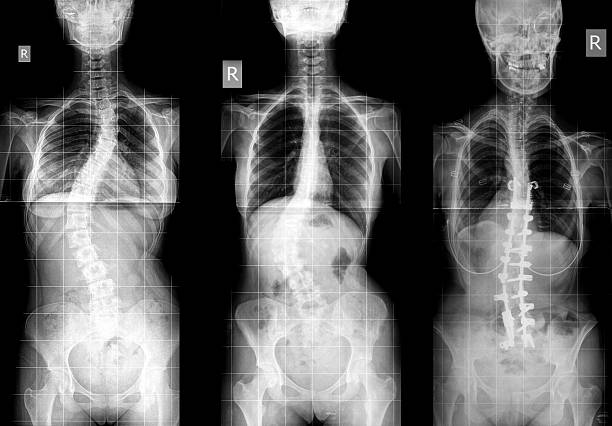

척추 측만증은 척추의 곡선이 비정상적으로 증가하여 등이 한쪽으로 치우치는 질환 입니다.

이로 인해 등이 비대칭적으로 변형되며 체형이 휘어지게 되는데요.

척추 측만증은 통증과 불편감을 유발할 뿐만 아니라 심각한 경우에는 신경 손상과 호흡 기능 저하를 초래할 수 있습니다.